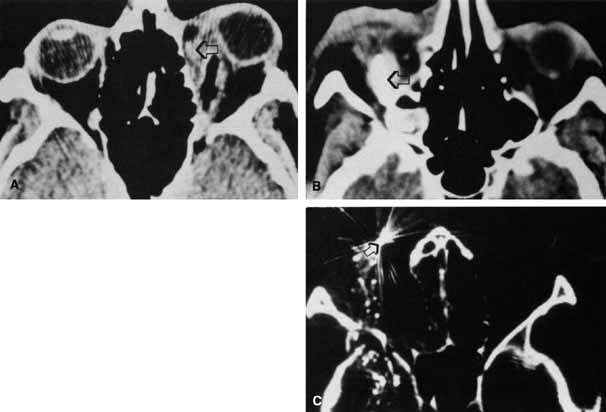

Fractures resulting in trapdoor incarceration of soft tissue and those generating an oculocardiac reflex are conditions warranting urgent surgical intervention, ideally within hours of injury. Trapdoor entrapment fractures occur more often in children, as their more flexible bone will fracture then bend back and incarcerate soft tissue and risk ischemic damage (Fig. 5 and 6). Morbidity results if there is a muscular or perimuscular soft tissue entrapment and earlier repair appears to yield better outcomes.40 Urgent intervention is also indicated if there is persistent oculocardiac reflex40,41 or when soft tissue entrapment in the fracture induces vagal symptoms of nausea, vomiting, syncope and possibly heart block.

Fig. 5 Right blowout fracture with prolapse of tissue into the fracture, causing limitation of upgaze.

Fig. 6 CT scan of trapdoor floor fracture. The inferior rectus is seen in the maxillary sinus (arrow). The fractured portion of the orbital floor has returned nearly to its original position.

Orbital emphysema results from air forced from the sinus into the orbit. This condition can occur with nose blowing or when orbital fat functions as a ball-valve over the fracture site.53 Emphysema of the soft tissue is appreciated by crepitus that can be palpated in the inflated eyelids. When the orbital septum remains intact, air is confined in the orbital space and can result in proptosis or reduction in motility (Fig. 12). Elevation of intraocular and intraorbital pressure can potentially compromise the retinal or posterior ciliary vasculature. Vision loss from this mechanism has been described,50,54,55 and this loss is considered an ophthalmic emergency. Intervention may include aspiration of air from an accessible site, such as the conjunctiva,50 or lateral canthotomy, with or without cantholysis, to decompress the orbit.52,54 More often, the condition is not sight-threatening and is self-limited. To avoid further inflation, the patient should be advised to not blow the nose or generate a Valsalva maneuver.

Fig. 12 In this patient (A) with right medial wall and tripod fracture, the mass effect of orbital air (B) (arrow) causes exophthalmos and contributes to hypophthalmos.